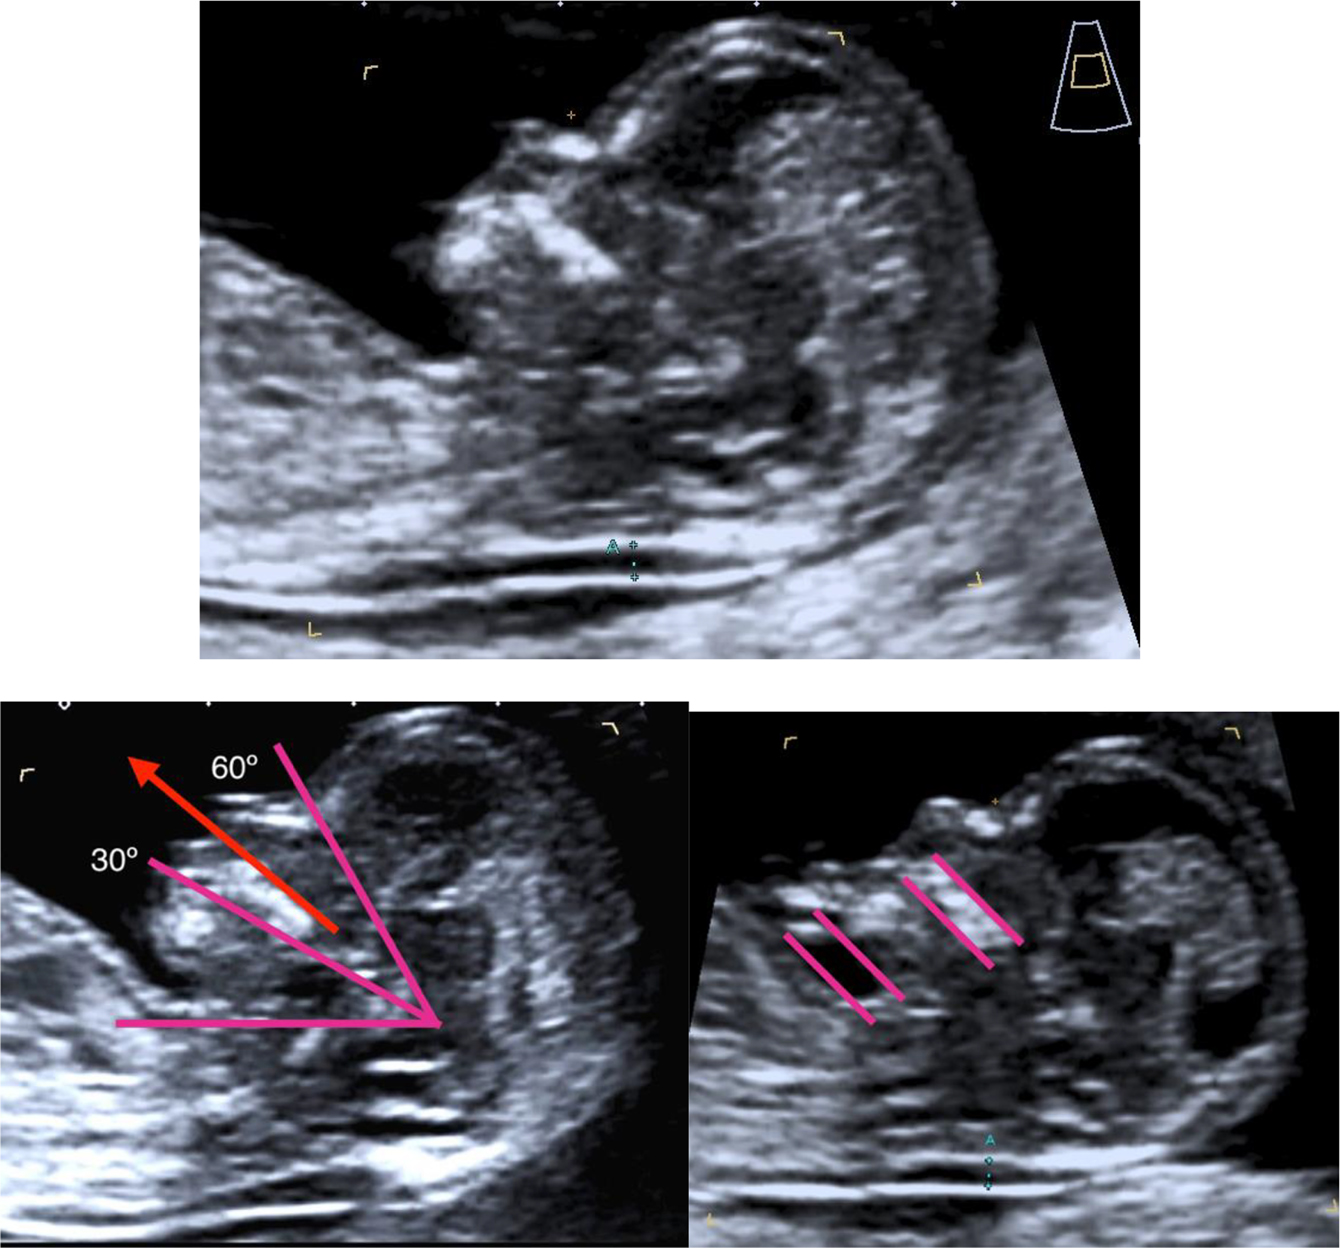

Figure 2 shows the optimal criteria for a correct NT measurement [12], [13], [22]

NT measurement standards.

Examination can be performed via transvaginal or transabdominal route. CRL between 45 and 84 mm. Magnification: the image should only include the head and upper thorax. Fetus in neutral position with the head in line with the spine (hyperflexion may result in a lower NT value, whereas an extended position may increase it). Criteria for ensuring a neutral head position: 1. Fetal palate angle should be between 30° and 60° with respect to the long axis. 2. The pocket of amniotic fluid between the lower chin and the thorax must be equal to or greater than the width of the palate. Midsagittal section with the presence of the echogenic tip of the nose, the rectangular shape of the palate, the diencephalon, and the nuchal membrane. The alveolar bone should not be visible. Measure the NT at the maximum echolucent space. Calipers on-on: the cross of the calipers should be placed on the inner borders of the nuchal fold. Reduce the gain to avoid incorporating the amnion Identification of the amniotic membrane separated from the fetus and possible umbilical cord interposition. If the umbilical cord is around the fetal neck, use the average of the measurements of NT above and below the cord.